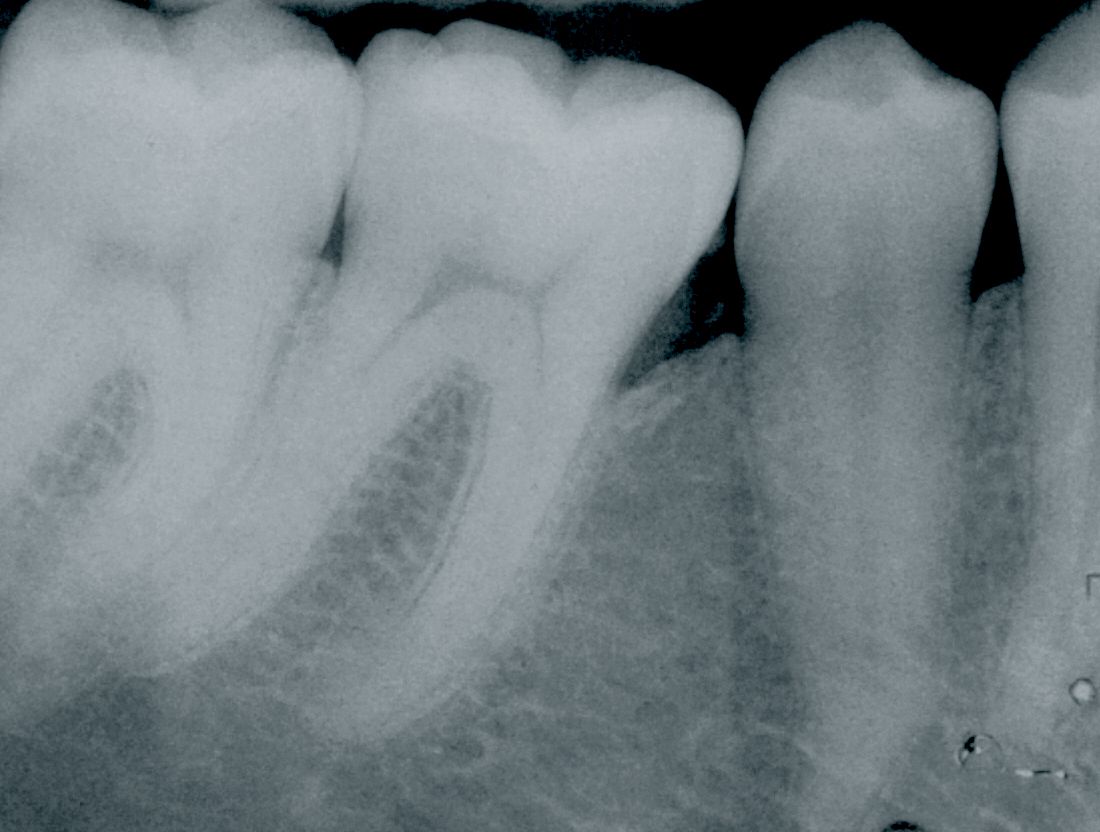

Initial situation

A systemically healthy 17-year old patient was diagnosed with a localized severe aggressive periodontitis. A pre-operative X-ray revealed an intra-bony defect in the mesial aspect of the first lower right molar (Fig. 1). Following the initial preparation, a remaining 10mm-periodontal pocket was evident (Fig. 2).

An immediate post-operative radiograph captured the bone graft in place (Fig. 7). The next sequence of radiographs shows the gradual bone fill of the defect at six months (Fig. 8), 3 years (Fig. 9), seven years (Fig. 10) and twenty years (Fig. 11).